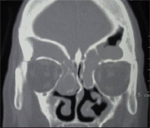

Examination is important to confirm the diagnosis. A look with an endoscope is essential. Investigations may be required to rule out an underlying allergy that may contribute to rhinosinusitis. If surgery is contemplated a CT (computed tomography) scan is requested.

scan of sinus